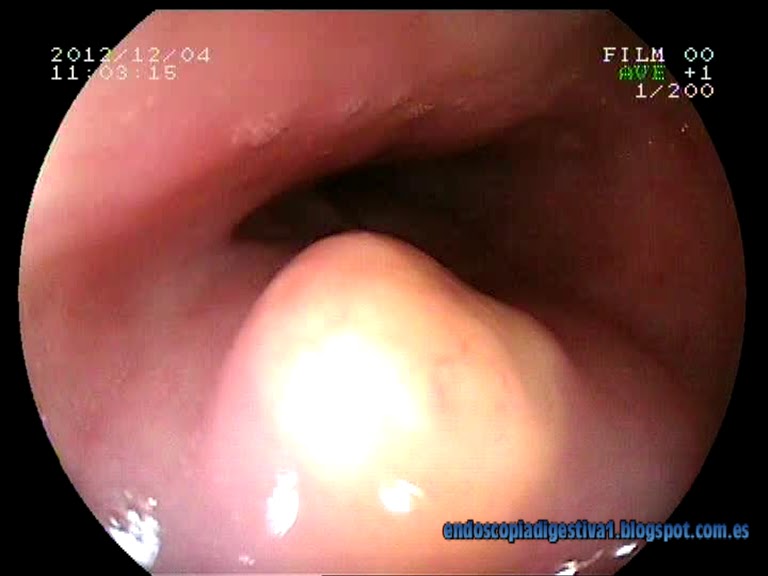

Paciente varón de 35 años de edad sin antecedentes de interés al que se le realiza una gastroscopia por síntomas moderados a severos de ERGE. En dicha exploración se aprecia una esofagitis de intensidad moderada así como una lesión de aproximadamente 1.5 cm de coloración amarillenta con mucosa de aspecto normal, dura al tacto del fórceps de biopsia en el esófago medio-distal (a unos 30 cm de la arcada dentaria). La histología de las biopsias realizadas (biopsia sobre biopsia) revelaron el diagnóstico de tumor de células granulares (tumor de Abrikossoff). Con idea de realizar una mucosectomía con bandas elásticas (técnica Duette) se realizó una ecoendoscopia radial que mostró una lesión homogénea, redondeada de 1.2 cm en esófago medio-distal hiperecogénica y bien delimitada, perteneciente a la 3ª capa esofágica (submucosa). Finalmente se realizó la mucosectomía sin complicaciones inmediatas, resecando en bloque la lesión. El estudio histológico confirmó el diagnóstico inicial y la resección completa de la lesión.

Los tumores de células granulares (tumor de Abrikossoff) son relativamente infrecuentes que se suelen localizar normalmente en la orofaringe, la piel y el tejido celular subcutáneo. En un 8-18 % de los casos se encuentra en el tubo digestivo, siendo el esófago la localización mas común (33 %). El 68 % de todos los tumores esofágicos se encuentran en esófago distal. Se cree que derivan de las células de Schwann. Generalmente son asintomáticos, aunque en ocasiones pueden sangrar o provocar disfagia y por ello se suelen diagnosticar de forma fortuita al realizar una gastroscopia por otros motivos. La mayoría de los tumores de células granulares son benignos, pero se han descrito casos de degeneración maligna en 1-3 % de los casos. Endoscópicamente se caracterizan por ser lesiones menores de 2 cm, en esófago distal, de coloración amarillenta con mucosa normal y de consistencia firme a la toma de biopsias. En la USE se caracteriza por ser de localización submucosa (2ª-3ª capa), bien delimitados e hiperecogénicos, que se suelen confundir por lo dicho con los lipomas. Se suele recomendar la realización de una PAAF por este motivo. Histológicamente se cracaterizan por ser postivos a S-100 con técnicas de inmunohistoquímica. Por la posible degeneración, se recomienda la resección endoscópica, siendo la mas usada la mucosectomía.